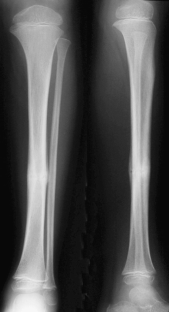

Fig. 4